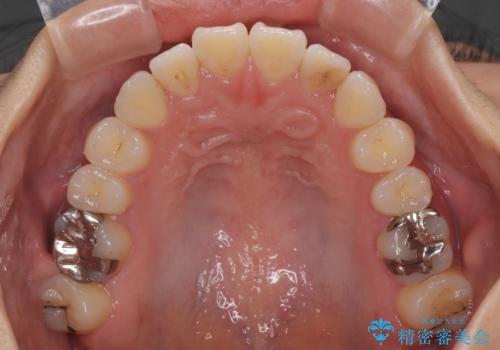

- 前歯の開咬を気にして来院された患者様です。

開咬の治療は、前歯を閉じるように動かすとともに、上下臼歯を圧下(骨内にめり込ませる)させることで進めて行きます。

インビザラインは臼歯の圧下を効果的に行えるため、インビザラインを用いて矯正治療を行うこととしました。